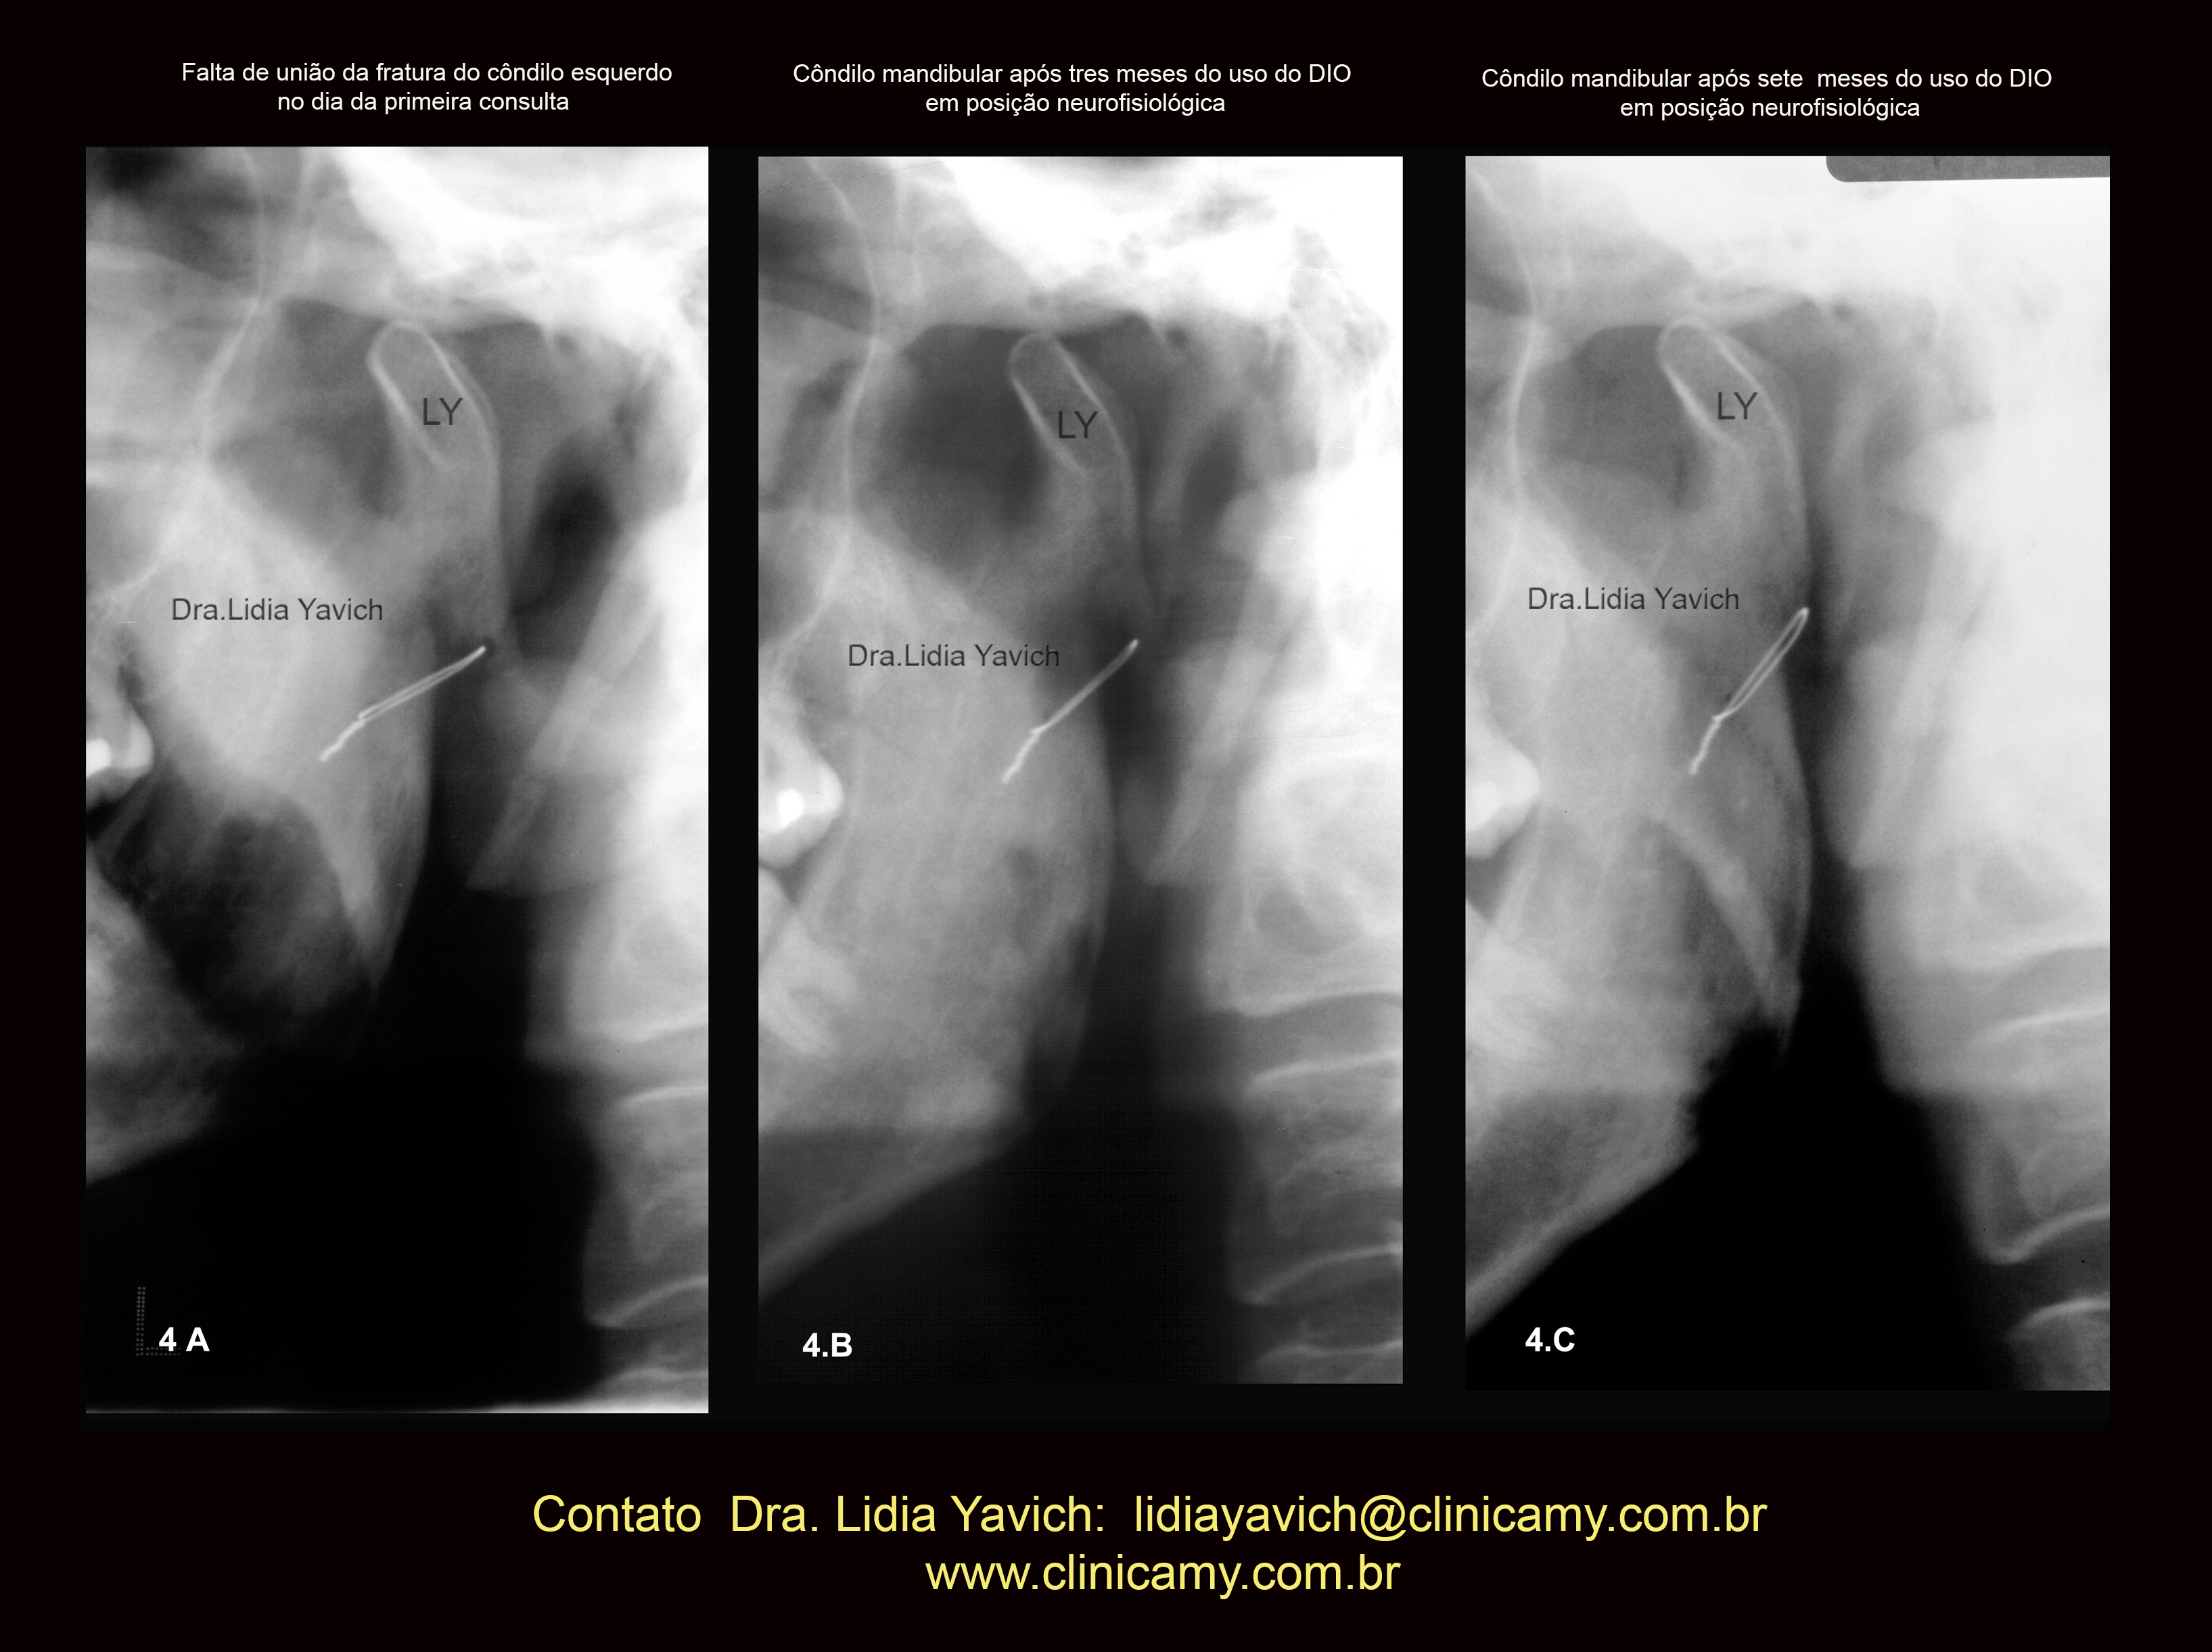

Uma segunda radiografia panorâmica foi solicitada três meses após o inicio do tratamento.

A nova radiografia panorâmica mostrou a melhora da posição do côndilo mandibular e finalmente quatro meses após este ultimo controle uma terceira radiografia panorâmica foi solicitada onde pode se observar a união da fratura.

Imagem comparativa do côndilo mandibular esquerdo na primeira radiografia panorâmica do paciente no dia da consulta (4A).

Segunda radiografia panorâmica três meses após (4B)

Terceira radiografia panorâmica (4C) quatro meses após o segundo controle mostrando a melhora da posição do côndilo mandibular e a união do osso.

OBSERVAR A VERTICALIZAÇÃO DO FIO METÁLICO DA CIRURGIA

INVERSÃO DA COR da imagem comparativa do côndilo mandibular esquerdo na primeira radiografia panorâmica do paciente no dia da consulta (4A), segunda radiografia panorâmica três meses após (4B) e terceira radiografia panorâmica (4C) quatro meses após o segundo controle mostrando a melhora da posição do côndilo mandibular e a união do osso.

OBSERVAR A VERTICALIZAÇÃO DO FIO METÁLICO DA CIRURGIA.

Imagem comparativa do côndilo mandibular esquerdo na primeira radiografia panorâmica do paciente no dia da consulta (4A), segunda radiografia panorâmica três meses após (4B) e terceira radiografia panorâmica (4C) quatro meses após o segundo controle mostrando a melhora da posição do côndilo mandibular e a união do osso.

As imagens frontais da oclusão habitual no dia da consulta, quatro e sete meses após iniciado o tratamento estão também inseridas nesta imagem.